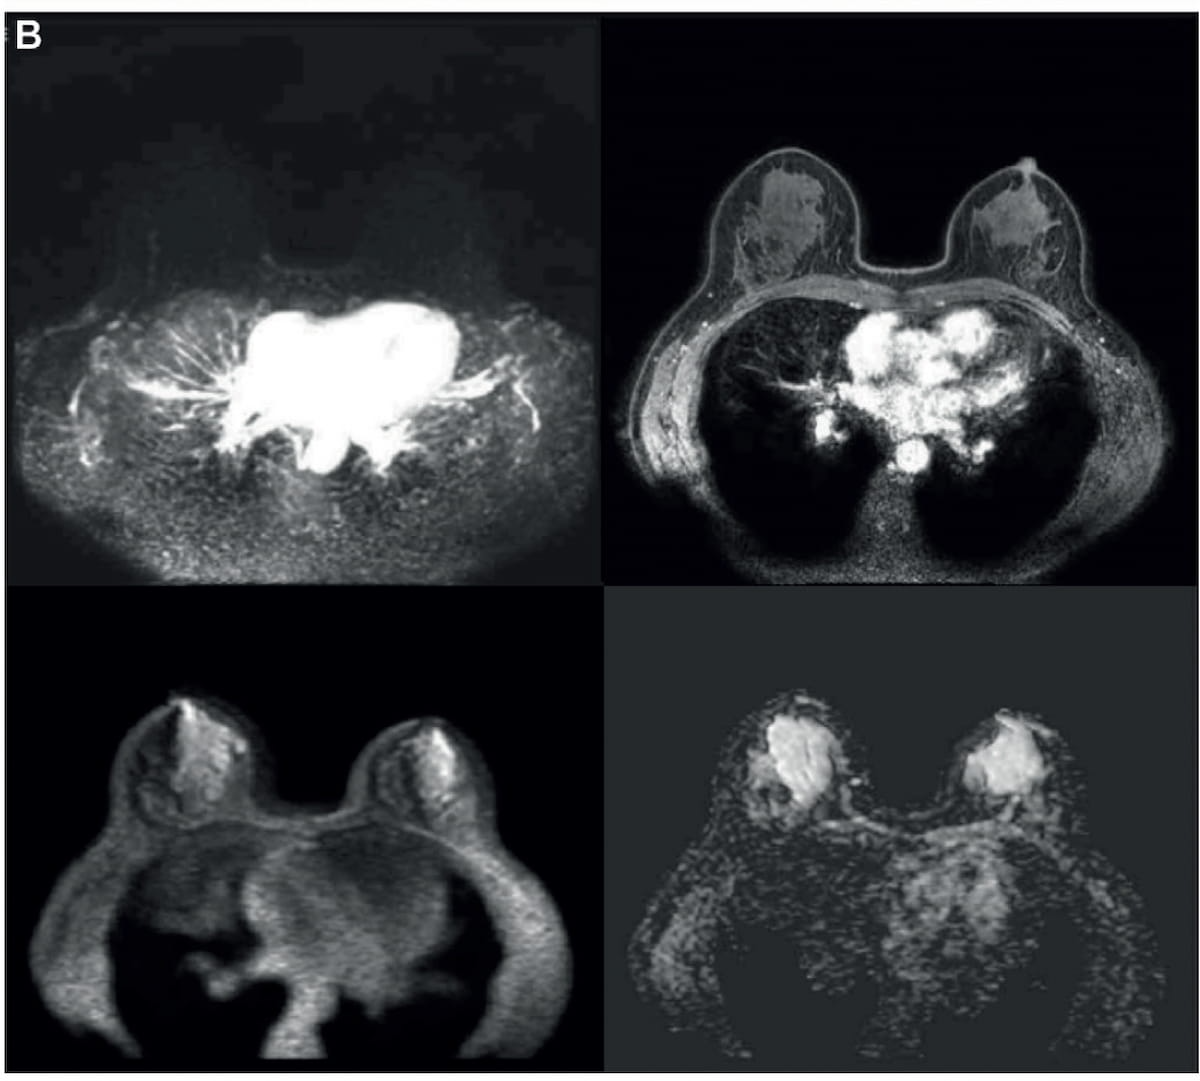

Here one can see the addition of diffusion-weighted imaging (DWI) to an initial abbreviated T1-weighted MRI series obtained prior to and up to 120 seconds after the injection of contrast material. In a new study, researchers found that abbreviated breast MRI offered comparable sensitivity and specificity for breast cancer in contrast to mpMRI. (Images courtesy of Radiology.)

In a secondary analysis from the Dense Tissue and Early Breast Neoplasm Screening (DENSE) trial, published earlier today in Radiology, researchers compared abbreviated breast MRI versus mpMRI in 518 women (median age of 53) who had extremely dense breasts and negative mammograms. The abbreviated MRI protocol included dual high-temporal low-spatial and low-temporal high-spatial dynamic T1-weighted MRI obtained immediately prior to and up to 120 seconds after injection of contrast material, according to the study.

The study authors found that the abbreviated MRI protocol offered 84.3 percent sensitivity and 73.9 percent specificity in comparison to 85.9 percent sensitivity and 75.8 percent specificity for mpMRI.

Researchers also noted a pooled reading time of 49.7 seconds for abbreviated breast MRI in contrast to 96.4 seconds for mpMRI. There was also an 81 percent reduction in approximate scan time for abbreviated breast MRI (3.5 minutes vs. 18.5 minutes), according to the study authors.